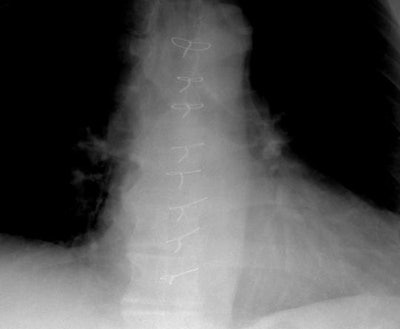

Mediastinitis:

The two coned views below compare the position of the sternal wires at discharge (following median sternotomy), and when the patient presented with fevers 3 weeks later- at which time there had been migration of a sternal wire- an indicator of mediastinitis.

Discharge: